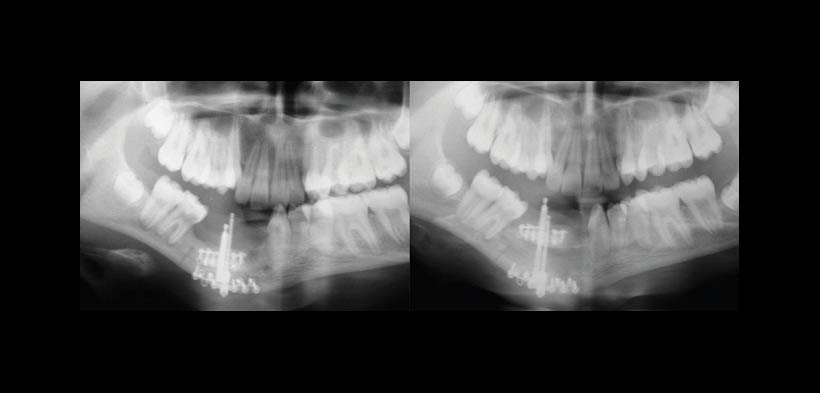

Fig. 5. Radiografías panorámicas antes y después de la distracción osteogénica, en la imagen de la derecha se muestra un mayor aumento en las dimensiones de la altura del hueso alveolar (radiografía tomada a los 6 meses después de la distracción osteogénica)